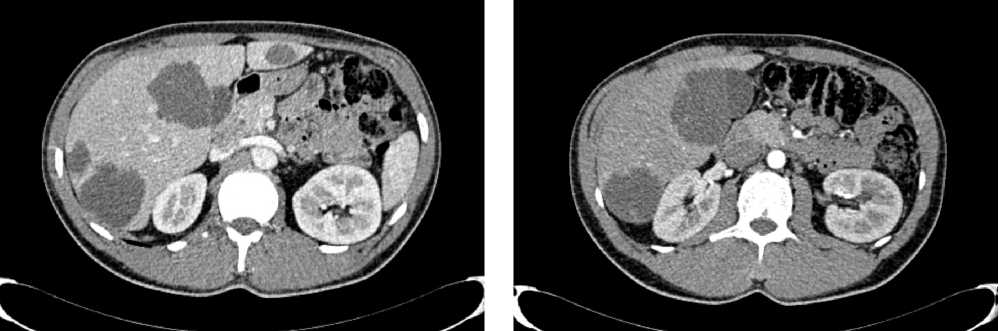

Клинический случай 1. Пациент А., 80 лет. В июле 2019 г., в связи с дообследованием по поводу генеза анемии 2 ст. при фиброгастродуоденоскопии (ФГДС), выявлена инфильтрация пилоробульбарного отдела желудка, компенсированный стеноз пилорического канала. По результатам гистологического и иммуногистохимического исследований обнаружена низкодифференцированная аденокарцинома с признаками dMMR/MSI-H (CPS = 50), HER2 отрицательная.

Выполнена компьютерная томография (КТ) органов грудной клетки, брюшной полости в июле 2019 г. Инфильтративных изменений в легких не обнаружено. Выявлено новообразование антрального отдела, малой кривизны и передней стенки желудка, распространяющееся на заднюю стенку, преимущественно на препилорический отдел. Имелись признаки локального перехода образования на большой сальник, гепатодуоденальную связку с периваскулярным ростом и признаками лимфоваскулярной инвазии. Многочисленные забрюшинные ЛУ сливались между собой в конгломераты размерами до 40 × 29 мм с частичным вовлечением почечных артерий. Также билобарно обнаружены немногочисленные очаговые образования в печени до 10 мм. Высказано подозрение на перитонеальный канцероматоз (рис. 3).

Рис. 3. Результаты компьютерной томографии органов брюшной полости у пациента 80 лет с диагнозом метастатический рак желудка с признаками микросателлитной нестабильности (июль 2019 г., до лечения)

Fig. 3. Results of a CT scan of the abdomen in an 80-year-old patient with metastatic MSI-H gastric cancer (July 2019, before treatment)

В результате обследования был установлен диагноз рака антрального отдела желудка (c)T4аN3вM1. По решению онкологического консилиума, учитывающего молекулярно-генетический профиль опухоли, а также возраст пациента, выраженность сопутствующей патологии (в анамнезе острое нарушение мозгового кровообращения (ОНМК), острый инфаркт миокарда (ОИМ), фибрилляция предсердий (ФП), постоянная форма), ограничивающей проведение ПХТ, была начата ИТ 1 линии пембролизумабом. С сентября 2019 г. по декабрь 2021 г. проведено 29 циклов ИТ 1 линии по схеме пембролизумаб в монорежиме с максимальным эффектом частичный регресс (рис. 4). Осложнений лечения не зарегистрировано.